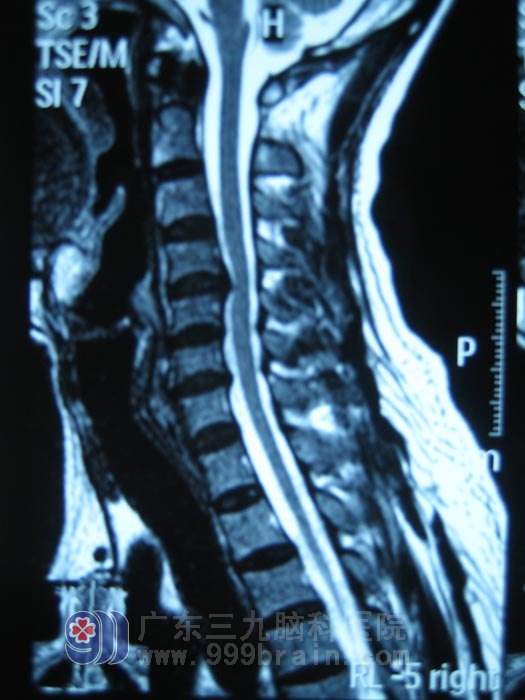

当天,接待小邹的是广东三九脑科医院脊髓神经外科 邹令芳主任。据小邹称,父亲今年53岁,于2月18日坐车上班时不幸发生车祸,当即昏迷,致使右侧面部损伤,头面部多处皮肤挫裂伤,在当地医院接受紧急救治后,邹先生得以清醒,脱离生命危险。为求进一步治疗,小邹将其父亲转入广州某大医院治疗,经检查发现,邹先生颅骨骨折、颅内有血肿;颈椎检查示颈6椎体前缘骨折、C4/5椎间盘突出(中央型)、C5/6椎间盘膨出。给予对症治疗及康复理疗,十余天后邹先生病情未见好转,颈部活动受限、四肢肌张力高、乏力,站立、行走困难,且小便解出困难,不得不插上尿管,便秘、胃口差、失眠。眼看父亲的病没有任何好转,小邹着急了,他辞掉工作,带着父亲的病历资料“网罗”广州各大医院,挨个医院挨个医院走,咨询专家意见。但几天下来,小邹总是满怀希望而去,失望而归,大多专家称其父亲的情况完全康复的希望渺茫。抱着绝望的心态,小邹在网上找到了广东三九脑科医院脊髓神经外科,并欣喜地发现了与其父亲情况类似的成功案例,抱着试试看的心态,小邹走进了广东三九脑科医院。脊柱脊髓外科邹令芳主任在查看其父亲的病情后,给予了他中肯的建议,并初步评估邹先生康复的可能性还是较大的。邹令芳主任的一席话让小邹看到了希望,他于次日将邹先生转入广东三九脑科医院治疗。www.999brain.com

入院诊断:1、急性脊髓损伤,2、颈6椎体前缘撕脱性骨折,3、颈椎病。

入院后予头颈胸支具固定,治疗予脱水、营养神经等对症治疗及康复治疗。3天后拔除尿管,邹先生能自解小便。十余天后,邹先生四肢肌张力较前减低,可自行站立行走,但双下肢乏力问题依然没有缓解。据邹令芳主任分析,邹先生四肢乏力与其与颈4/5椎间盘突出,相应硬膜囊受压有明显关系,行微创手术——椎间盘内射频热凝疗法可很好地改善此症状。于是,在征得邹先生家属同意的情况下,3月30日,邹先生在局麻下接受了颈椎间盘突出射频热凝术,术后继续行颈椎制动,予抗炎、消肿、营养神经药物等对症治疗及康复治疗。十余天后邹先生得以康复出院,出院时肢体肌力恢复正常,肌张力基本恢复正常,可以很好的完成站立、行走及上下楼梯等,生活能自理,康复出院。www.999brain.com

术前